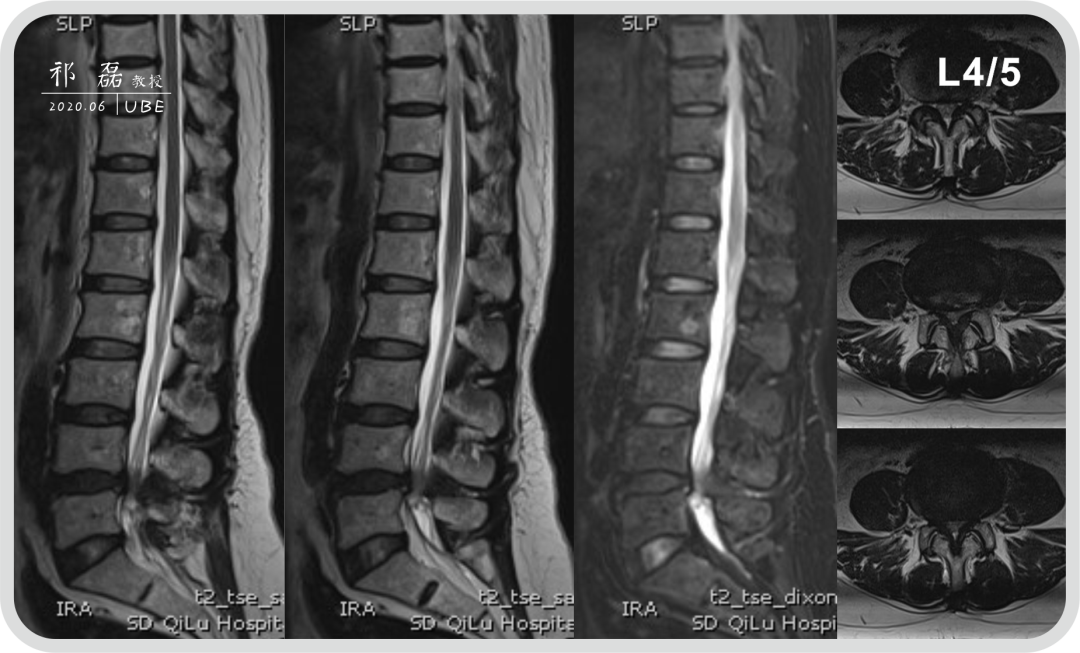

患者:吴某,女,53岁,腰痛及双下肢疼痛麻木5年余,加重1月余,间歇性跛行约200米。于近日入我院查体,下腰椎棘突及椎旁肌深压痛,双下肢感觉运动正常。双侧直腿抬高试验(-),双侧踝反射(-),入院诊断为:腰椎管狭窄症。

图3:腰椎MRI